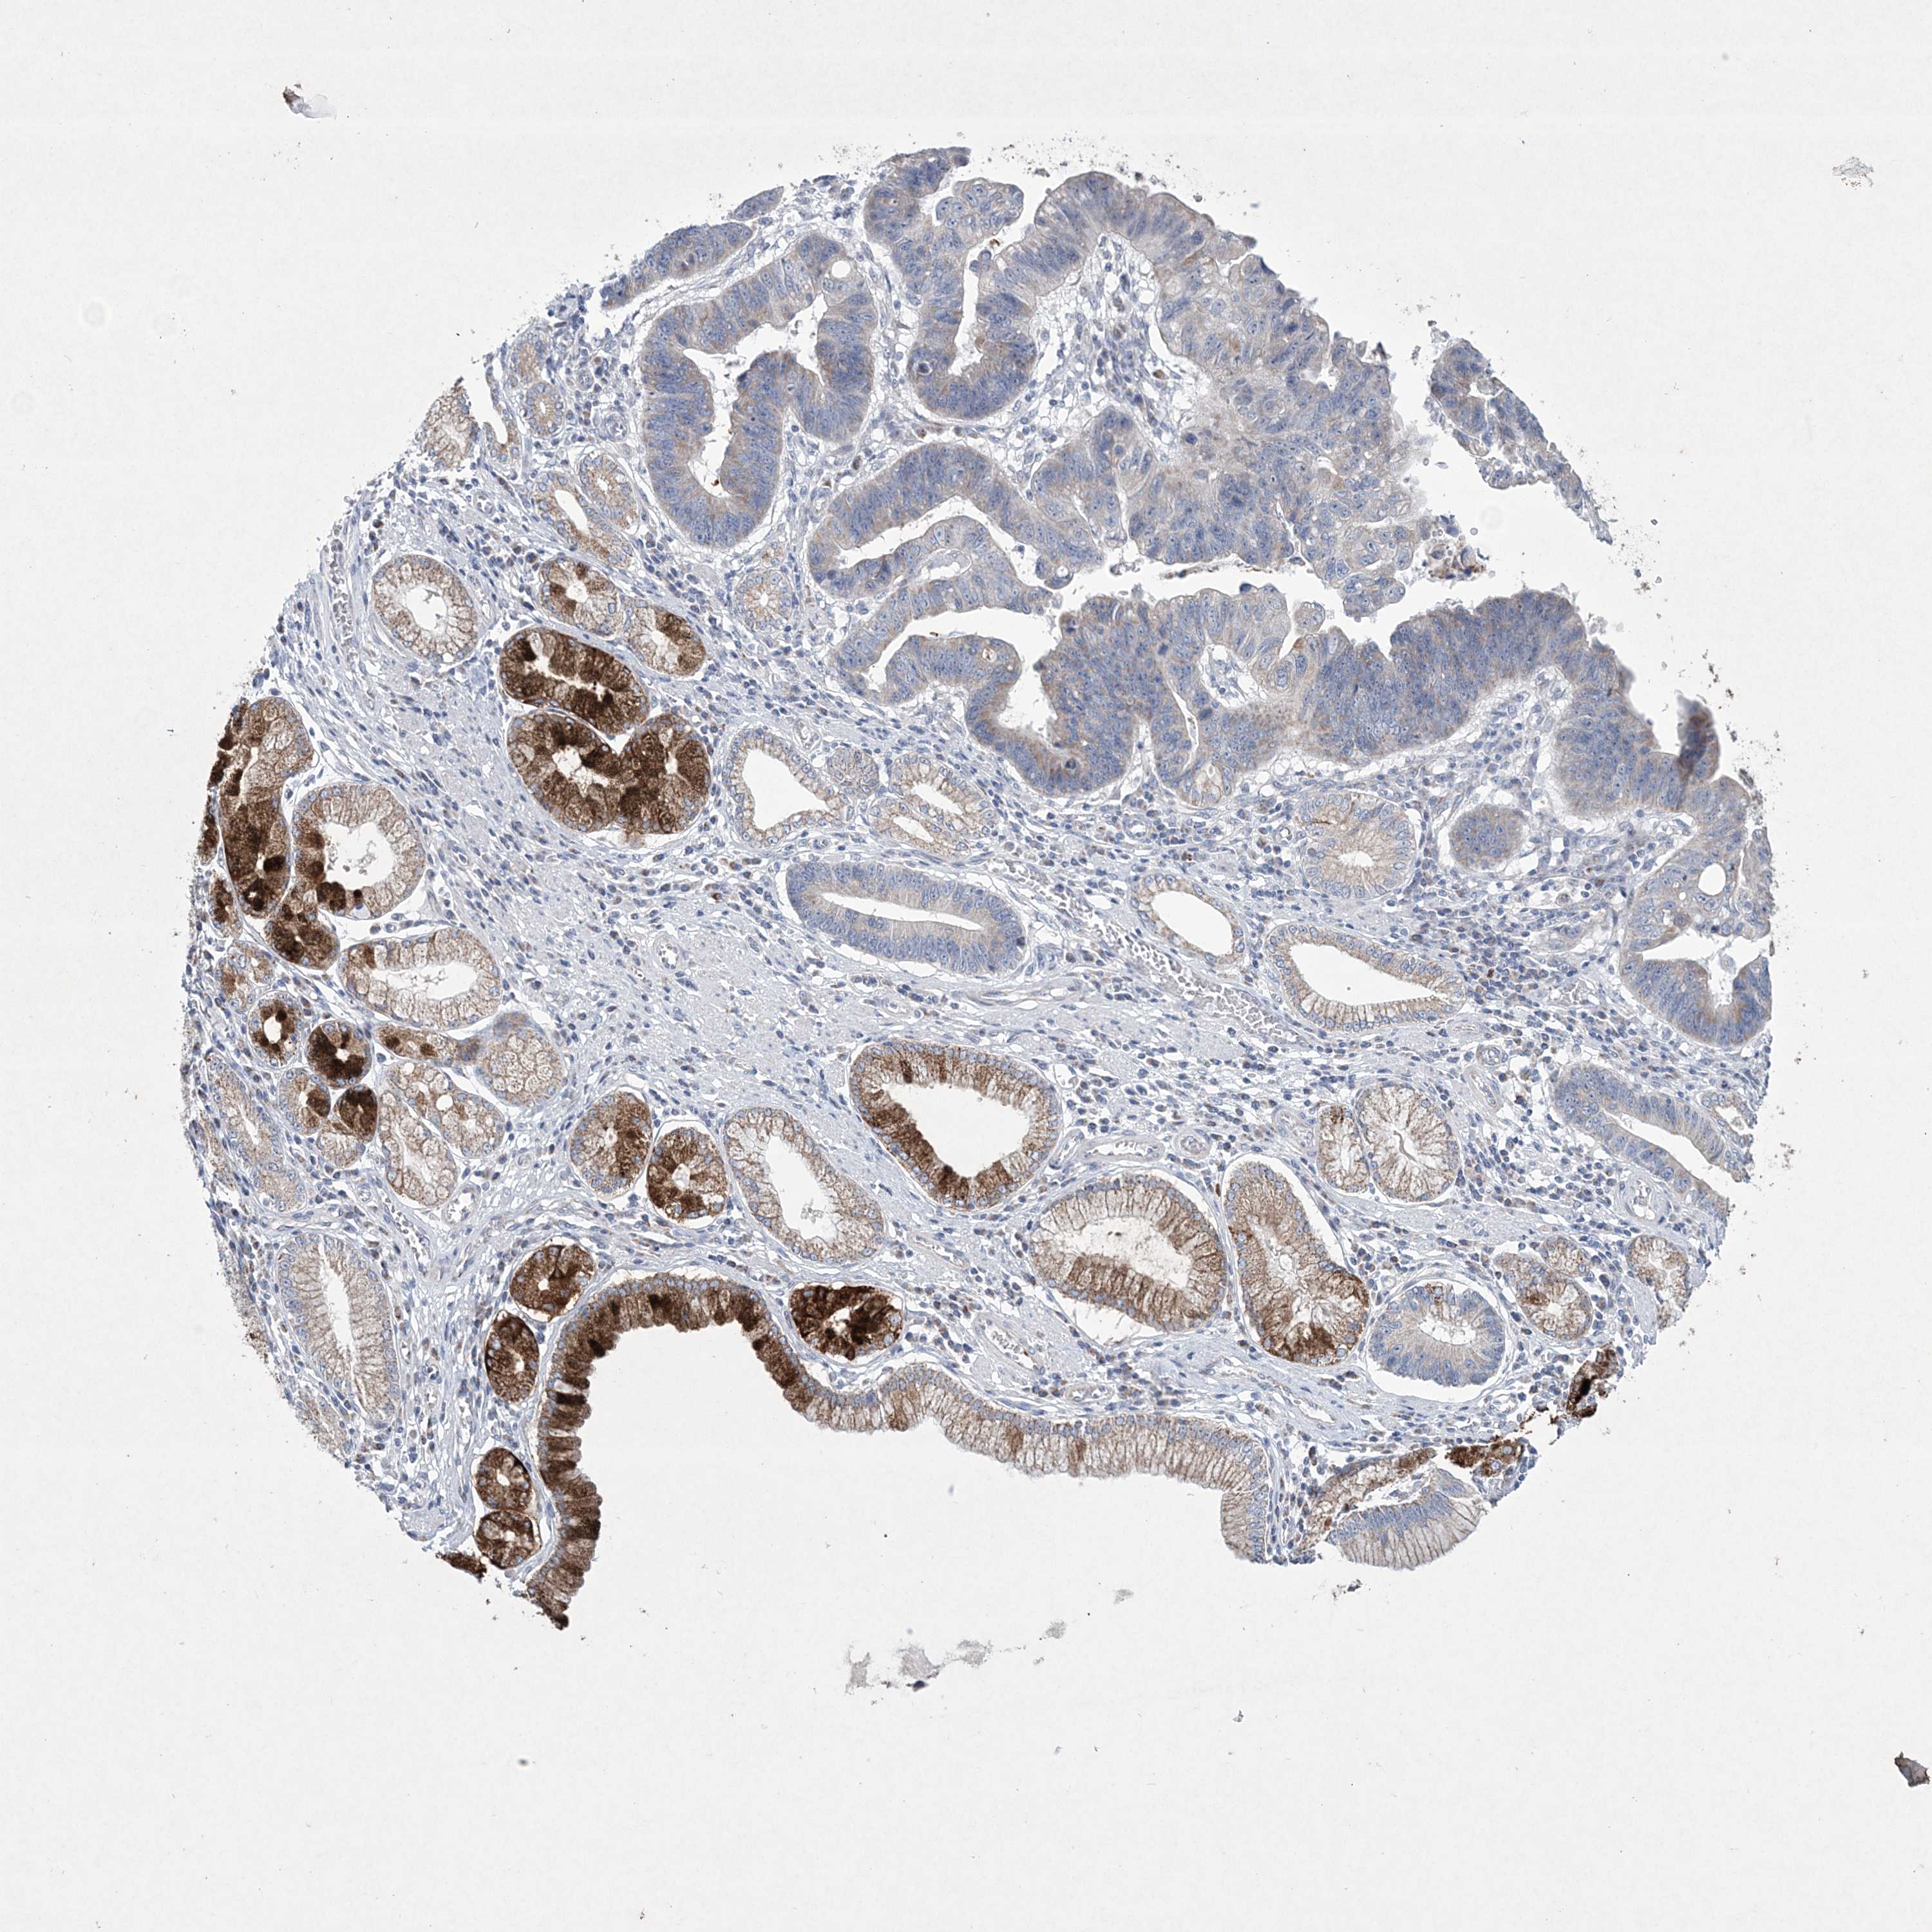

STOMACH CANCER - Protein expressioni

A mouse-over function shows sample information and annotation data. Click on an image to view it in a full screen mode. Samples can be filtered based on level of antibody staining by selecting one or several of the following categories: high, medium, low and not detected. The assay and annotation is described here.

Note that samples used for immunohistochemistry by the Human Protein Atlas do not correspond to samples in the TCGA dataset.

Antibody stainingi

Antibody staining in the annotated cell types in the current human tissue is reported as not detected, low, medium, or high, based on conventional immunohistochemistry profiling in selected tissues. This score is based on the combination of the staining intensity and fraction of stained cells.

Each image is clickable and will lead to virtual microscopy that enables deeper exploration of all samples and also displays staining intensity scores, fraction scores and subcellular localization as well as patient and tissue information for each sample.

Antibody HPA035701

Staining

High

Medium

Low

Not detected

Intensity

Strong

Moderate

Weak

Negative

Quantity

>75%

75%-25%

<25%

None

Location

Nuclear

Cytoplasmic/membranous

Cytoplasmic/membranous,nuclear

Adenocarcinoma, NOS